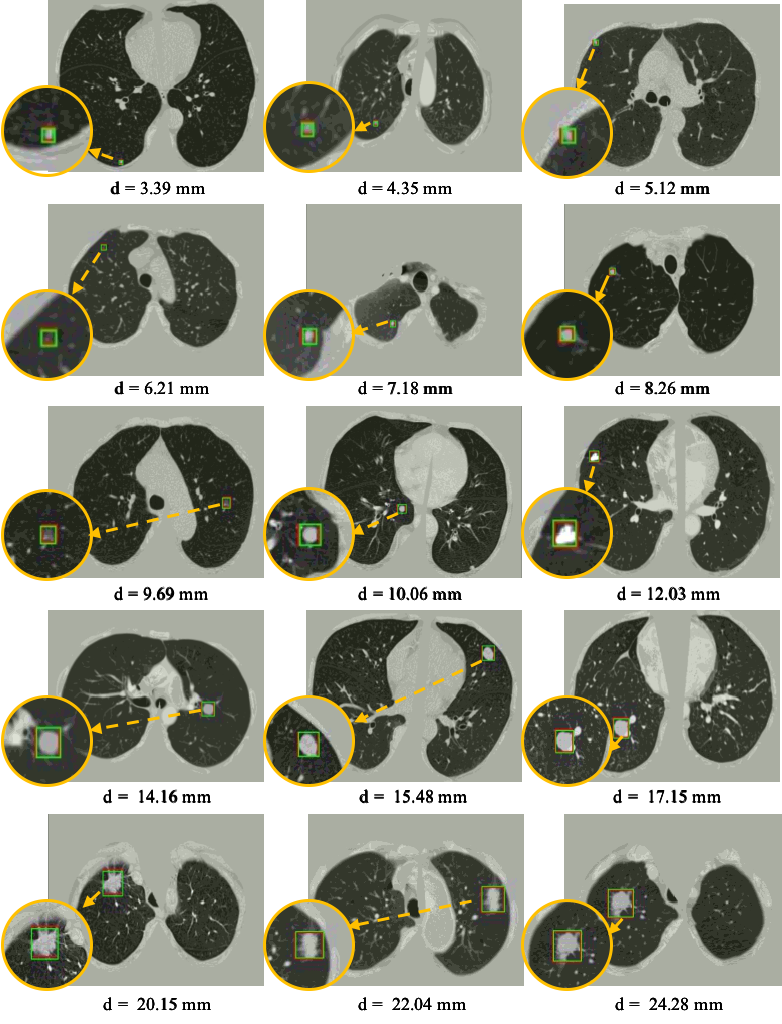

Table 4 shows the FROC evaluation results of our proposed method compared with state-of-the-art methods on LUNA16 at 1/8,1/4,1/2,1,2,4,818141212481/8,1/4,1/2,1,2,4,8 false positive levels. The highlighted numbers in the table indicate the best performance within each column. Since the pre-trained model is not used in most state-of-the-art methods, for a fair comparison, all the methods are tested on LUNA16 dataset followed the same FROC evaluation without the pre-trained model. As shown in the table, our framework outperforms 5.5%percent5.55.5\% average sensitivity than the best result of other methods. In addition, the proposed framework achieves the best performance at every FP level. As previously mentioned, the CAD system is not only required a high sensitivity, but also high specificity. Table 4 demonstrates that the false positives are greatly reduced by the proposed HS2 network. 3DFPN-HS2 obtains a highest 97.14%percent97.1497.14\% sensitivity at 222 FPs per scan. In addition, for the FP of 1/8181/8, 1/4141/4, and 1/2121/2 per scan, the proposed framework still remains a high sensitivity above 90%percent9090\%. The experimental results show that 3DFPN-HS2 reaches a state-of-the-art performance for high sensitivity and specificity lung nodule detection. The illustration of nodule detection results is shown in Figure 7.

Refer to caption

Figure 7: Visualization of some detected true nodules with different sizes from 3mm to 25mm in diameter d𝑑d by our proposed 3DFPN-HS2 framework. For a better visualization, the detected nodule regions are zoomed in as shown in the orange circles. The green box indicates the predicted region and the red box represents the ground-truth. Some of the red boxes are not clearly observed because they are perfectly overlapped with the green boxes. The results demonstrate that our 3DFPN-HS2 framework is capable to accurately detect lung nodules of different sizes from CT scans.